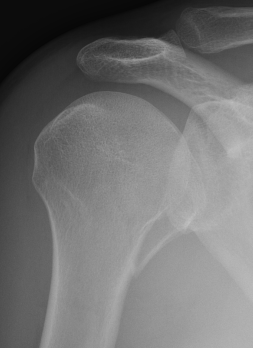

Two part

Displaced greater tuberosity fracture

Displaced lesser tuberosity fracture

Two part proximal humerus fracture

Two part proximal humerus fracture dislocation posterior